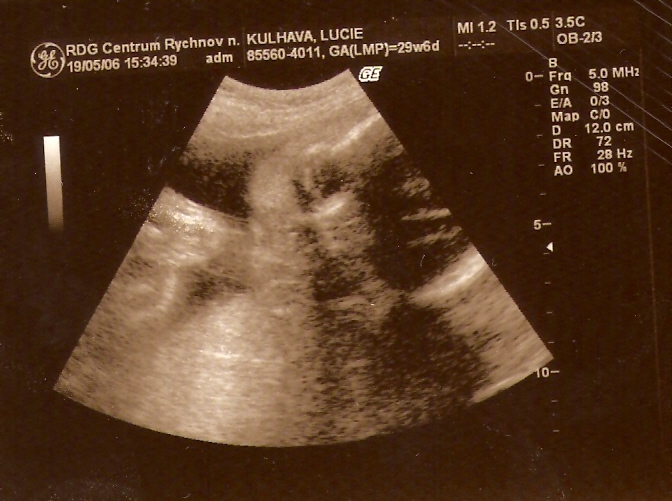

...do třetice všeho dobrého a vlastně naposledy (před porodem) mě mamka s tátou viděli 19. KVĚTNA 2006 /30. týden/...